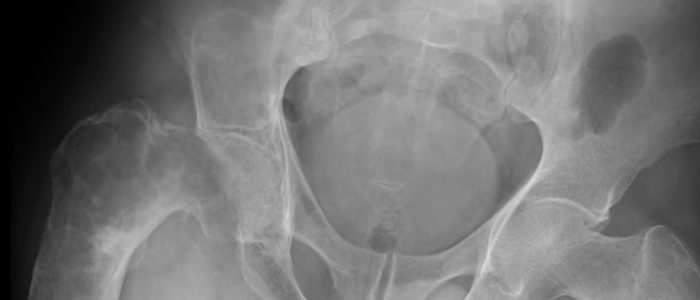

Первым этапом в диагностике есть визуальный осмотр образования на гинекологическом кресле, пальпация и устный опрос. Это дает возможность определить само наличие проблемы и распознать ощущения пациента, с нею связанные. Также поможет выяснить возможные причины, повлекшие проблему. Для более детальной картины заболевания проводят УЗИ с красящим веществом (цветное допплеровское картирование). При этом определяется размер, форма и структура образования, а также специфика кровоснабжения опухоли. В дополнение или как самостоятельную методику диагностирования можно применять МРТ и КТ. Гистологическое исследование на наличие раковых клеток проводят с удаленного материала, после операции.